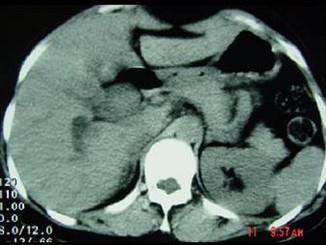

问题 女,35岁,右上腹痛一月,黄疸进行性加重,AFP阴性,消瘦乏力,影像检查如图,最可能的诊断为 ( )

选项 A、原发性肝癌 B、肝血管瘤 C、胆管癌 D、局灶性脂肪肝 E、肝转移癌

答案 C